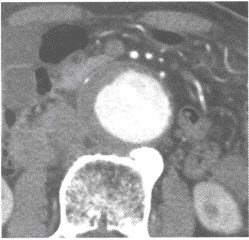

男性,70岁。行腹部CT增强扫描,发现腹主动脉异常如下图。

第1题,共2个问题

(单选题)对该病术前评价和术后随访的最佳方法是()

A:X线平片

B:DSA

C:MSCTA

D:超声成像

E:MRI

第2题,共2个问题

(单选题)应诊断为()

A:主动脉血栓形成

B:主动脉硬化

C:主动脉瘤并附壁血栓

D:主动脉夹层动脉瘤

E:主动脉破裂